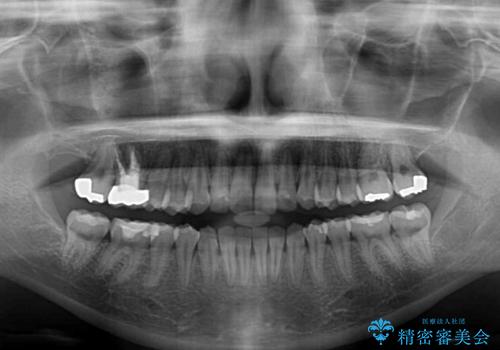

矯正治療は8ヶ月ほどで終了し、速やかに虫歯治療に移行することができました。

保険治療で用いる樹脂(コンポジットレジン)で行った虫歯治療は、周辺が変色して汚くなっていましたが、下顎はセラミックインレーで審美的に、上顎はPGAインレーで歯に負担の少ない治療を行うことができました。